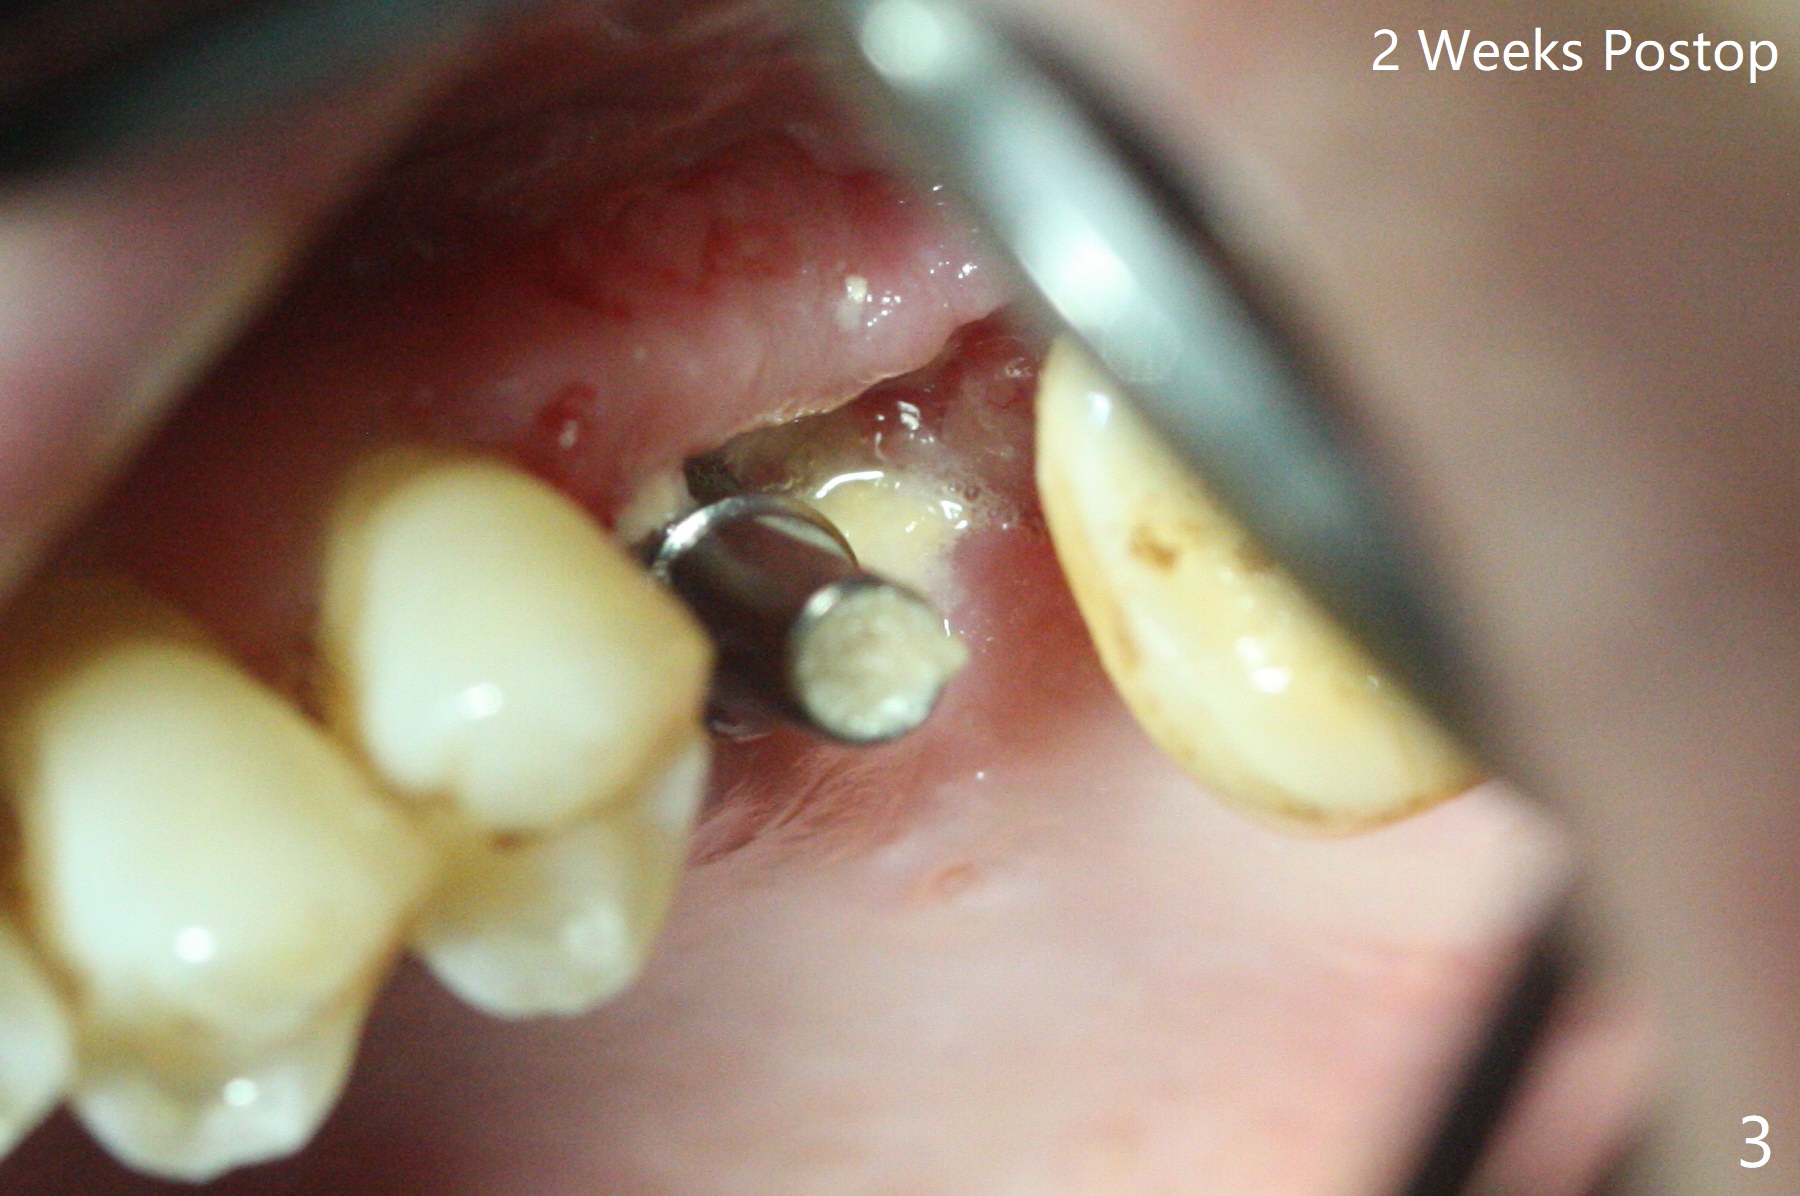

50岁男左上6严重斜型骨质吸收(意味着牙龈特别厚,有可能植入许多骨粉),拔除近中残根后,切开翻瓣,利用导板,4.5x11毫米植体不仅有意近中植入(补偿斜型骨质吸收而造成远中偏移),而且种得表浅(避免使用异常长的基台,改善冠根比例,图一),之后堆入不少粘性骨粉(图二:*),覆盖PRF膜,减张缝合(挺困难),牙周敷料。术后两周,敷料脱落,伤口裂开,但愿骨粉丢失不会太多(图三,四),树脂敷料可能更稳当。术后4个月骨粉好像覆盖远中曾经暴露螺纹(图五:^)。术后四个月伤口愈合(图六),临时牙冠大约3个月。粘固前局部牙龈健康,螺丝扭力30 Ncm。